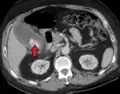

| Acute cholecystitis as seen on CT. Note the fat stranding around the enlarged gallbladder. | |

Right upper quadrant abdominal ultrasound is most commonly used to diagnose cholecystitis.[1][26][27] Ultrasound findings suggestive of acute cholecystitis include gallstones, pericholecystic fluid (fluid surrounding the gallbladder), gallbladder wall thickening (wall thickness over 3 mm),[28] dilation of the bile duct, and sonographic Murphy's sign.[13] Given its higher sensitivity, hepatic iminodiacetic acid (HIDA) scan can be used if ultrasound is not diagnostic.[13][14] CT scan may also be used if complications such as perforation or gangrene are suspected.[14]